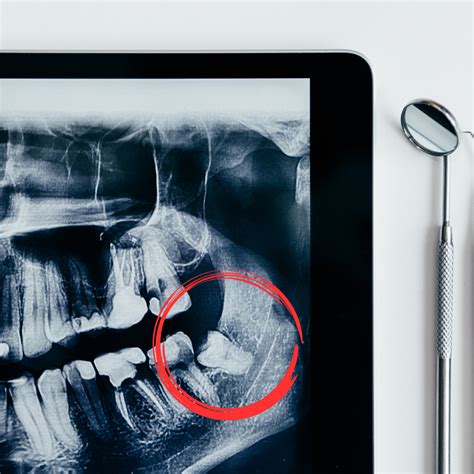

Diagnóstico

Para saber si tienes o no muelas del juicio, los dentistas utilizamos varios métodos de diagnóstico. Sin embargo, la manera más efectiva de confirmar la presencia o ausencia de muelas del juicio es mediante radiografías dentales, como las panorámicas. Este diagnóstico temprano es fundamental ya que permite tomar ciertas decisiones que evitarán problemas más graves con el transcurso de los años.